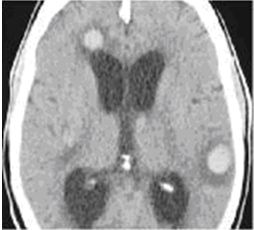

Hình 2. Hình ảnh di căn não đa ổ có chảy máu trong u trên phim CT trước tiêm thuốc của bệnh nhân ung thư phổi không phải tế bào nhỏ

Hình 3. Hình ảnh di căn não đa ổ có lắng đọng canxi trên phim CT trước tiêm thuốc (A) và sau tiêm thuốc (B) của bệnh nhân ung thư dạ dày loại biểu mô tuyến chế nhầy có chảy máu trong u